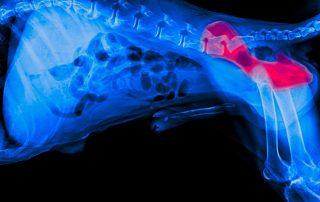

Canine TPLO ~ Tibial Plataeu Leveling Osteotomy Orthopedic Surgery with veterinarian Dr. Ram Singh

If your dog has torn their Cranial Cruciate Ligament (CCL) – the equivalent of the ACL in humans – we may recommend a TPLO (Tibial Plateau Leveling Osteotomy). The is one of the most common and effective orthopedic surgeries performed ondogs!

- What is the CCL and Why Does it Tear? The CCL is a major ligament in your dog’s knee (stifle) joint. It keeps the upper leg bone (femur) from sliding backward off the lower bone (tibia). A dog’s CCL can tear from sudden trauma or because of a chronic, gradual degeneration exacerbated by the slope of their tibial plateau. Every time your dog puts weight on the leg, this slope causes a forward thrust, stressing the CCL until it eventually fails.

- What Does TPLO Surgery Do? The goal of TPLO is NOT to repair the torn ligament (it’s often far too damaged), but to completely eliminate the need for it! 1. The Cut: A specific semicircular cut (osteotomy) is made into the top part of the tibia. 2. The Leveling: The surgeon rotates the cut piece of bone until the problematic slope is nearly level. 3. The Fix: A bone plate and screws are secured to the bone to hold this new, leveled angle in place.

- The Result? When your dog bears weight, the forward thrust is gone. The new, level surface creates a stable joint, allowing your dog to walk without the instability caused by the torn ligament.

- Key Takeaway TPLO is a permanent, biomechanical solution that gives your dog a stable, functional knee joint for years of happy, active life!